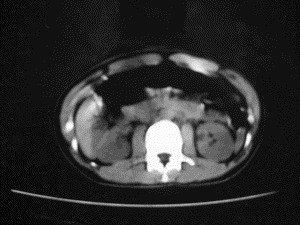

患者女,20岁,被车撞伤3小时,pe:全腹肌紧张,压痛反跳痛,以右上腹为著,肠鸣音减弱。有手术结果。![]() ![]() ![]() ![]() ![]() ![]() ![]() ![]() ![]() ![]() ![]() ![]() ![]() ![]() ![]() ![]() ![]() ![]() ![]() ![]() ![]() jiajie发言: ![]() 考虑空腔脏器穿孔。 dyqct发言:考虑:1、肝左叶外侧段断裂伤伴少量腹血。2、空腔脏器穿孔。 fangzheng发言:仅见腹腔内游离气体,提示空腔脏器穿孔。 guoke发言:胃内密度增高,肠腔内充满气体,考虑肠腔破裂出血 mmg94发言:胃后壁见一增厚软组织密度影,肝左叶前见游离气体影,左腹腔内局部肠管壁、系膜增厚。并见类圆形软组织。以上征象提示消化道管腔破裂,小肠、肠系膜挫裂伤,腹腔血肿形成。 拾荒者发言:肝实质密度不均匀,胃内见不均匀高密度影。考虑:肝挫裂伤,胃内应激性溃疡出血。 守望可可西里发言: 以下是引用jiajie在2006-6-20 15:49:00的发言:[br] [br][br]考虑空腔脏器穿孔。jiajie老师,我鼓起了很大的勇气才决定给您唱个反调儿,如果我错了,请您一定给我指出来,谢谢您了。我反复看了解剖图谱,觉得您所说的“考虑空腔脏器穿孔”上图所用箭头标明的不是游离气体。请您看以下几幅图片: ![]() ![]() ![]() ![]() ![]() ![]() ![]() ![]() 再请您看向医生老师发表的解剖图谱3幅 ![]() ![]() ![]() 这以下几幅图,我认为是肝包膜下积血。不过,说实在话,我没有发现有明显的肝挫裂伤。不对的地方请您一定指出来,再次感谢您了,jiajie 老师! ![]() ![]() ![]() ![]() 这下面几幅图片,我认为有明显的左中上腹部小肠损伤。 ![]() ![]() ![]() ![]() ![]() ![]() ![]() ![]() jiajie 老师,估计我说的是错误的,但我实在闹不明白,请您一定不要笑话我,并指出我的错误,以便于我减少工作中的失误。再次感谢您了,jiajie 老师! 至于胃内的不均匀高密度,我认为拾荒者战友说的有道理,胃内应激性溃疡出血和胃内容物混合所致。 手术结果:左肝叶(iv段)前缘长约8cm挫裂伤口,舌叶根部下< |